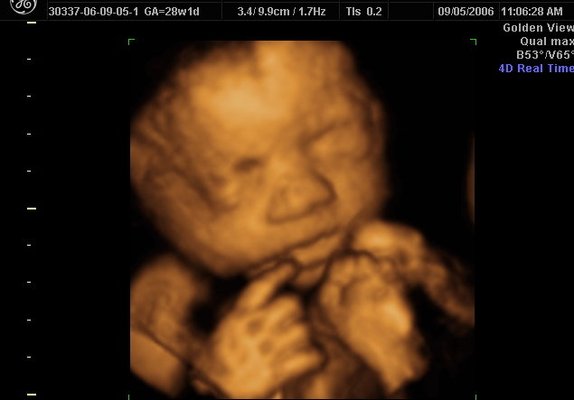

3d Ultrasound